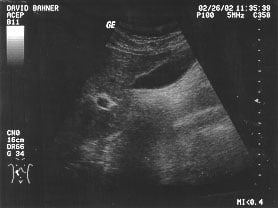

Aorta - renal (unlabeled)